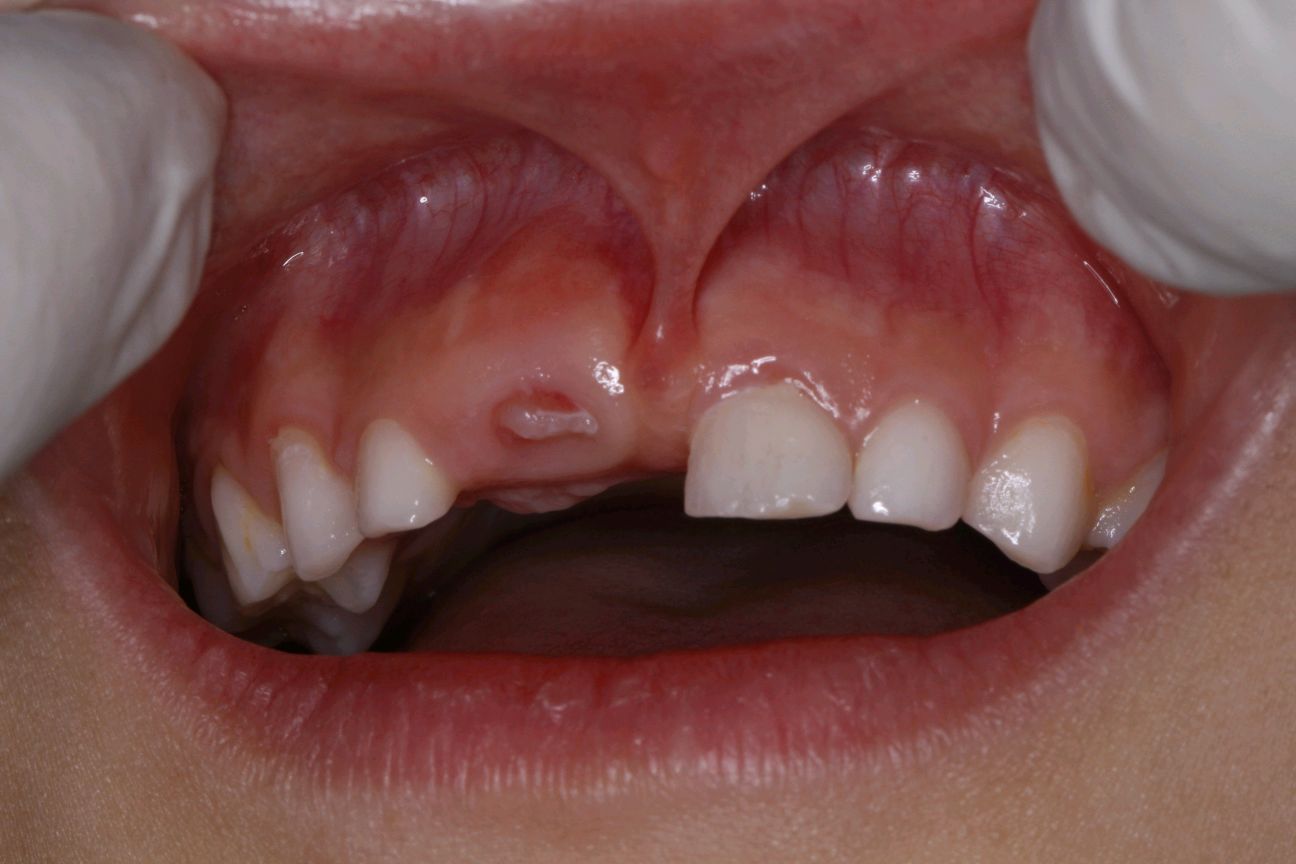

患者女,7 岁。前上唇系带过短,系带的牵拉使门牙缝隙变大。张口时上唇不能上翘,影响正常发音,前来我院就诊。

治疗方案:唇系带切除术。

术前